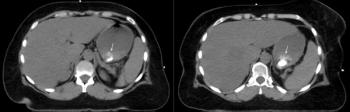

A 57-year-old woman with a history of stage IIB breast cancer (ypT2N1M0) status post neoadjuvant chemotherapy and left partial mastectomy presents to the radiation oncology clinic for CT simulation in preparation for breast radiotherapy. Noncontrast CT scan incidentally found the abnormality depicted with arrows below. What is your diagnosis?